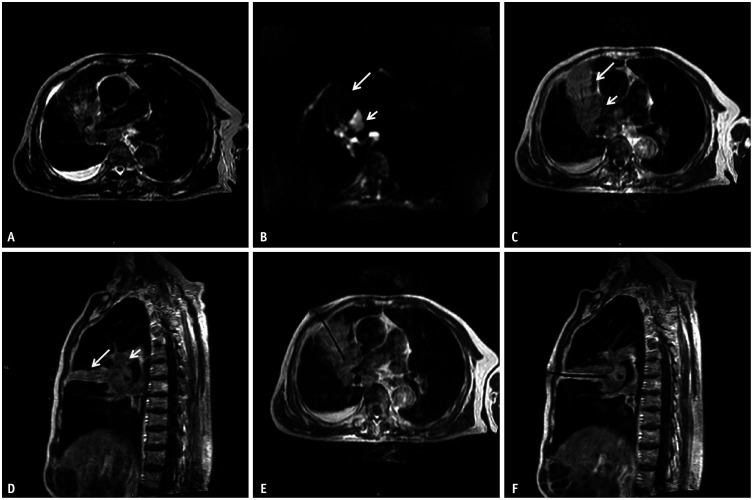

Materials and methods: In this single-center study, MRI-guided percutaneous coaxial cutting biopsy was performed for 107 suspicious central lung lesions with associated post-obstructive atelectasis in 107 patients between July 2015 and December 2020. A fast T2-weighted imaging (T2WI)-turbo spin echo (TSE) sequence and an enhanced fast T1-weighted imaging (T1WI)-TSE sequence were used to identify, localize, and biopsy lung lesions, and diffusion-weighted imaging (DWI) was used as a supplementary sequence for identifying the lesion location. The final diagnosis was confirmed by surgical histopathology or clinical follow-up for a minimum of 24 months. The sensitivity, specificity, and accuracy for diagnosing lung malignancies were calculated, and the complications were recorded for each case.

Results: Using multiparameter MRI, central lung lesions could be clearly distinguished from post-obstructive atelectasis in 96 patients (89.7%). The sensitivity, specificity, and accuracy of MRI-guided percutaneous biopsy for diagnosing lung malignancy was 97.0% (98/101), 100% (6/6), and 97.2% (104/107), respectively. Self-limited hemoptysis occurred in three patients. Pneumothorax occurred in five patients, of which none required pleural drainage. No serious procedure-related complications were observed.